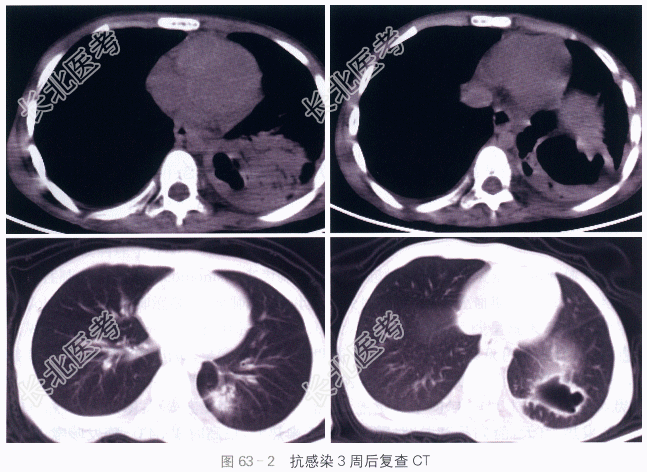

读片分析:CT示:左肺下叶大片实变影,内部肺纹理模糊不清,可见少量支气管充气影,背段及后基底段可见两个类圆形空洞形成,空洞壁较厚,厚度均匀,内壁较光整,后基底段空洞底部见少量液平,未见明显结节及肿块影,外壁不清;所见肺门及纵隔淋巴结无明显肿大;左侧胸腔少量积液。抗感染3周后复查,示左肺下叶大片实变影吸收、消散,下叶背段较小的空洞影闭合、消失,局部仅见少量渗出影及少许纤维条索;后基底段空洞较3周前缩小,空洞壁变薄,周围见少量纤维条索,局部可见少量胸膜增厚及粘连影。